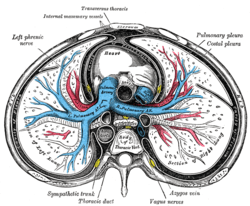

Transverse section of thorax, showing relations of pulmonary artery. Pulmonary vessels, seen in a dorsal view of the heart and lungs.

Pulmonary vessels, seen in a dorsal view of the heart and lungs. Base and diaphragmatic surface of heart.